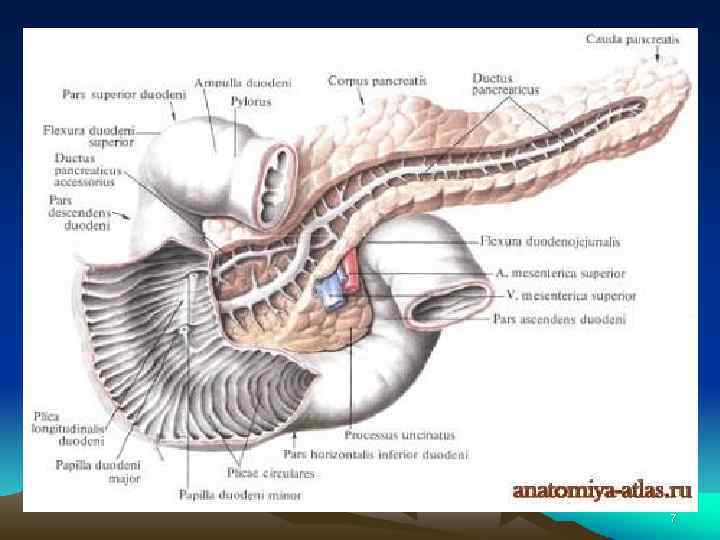

• Поджелудочная железа, pancreas — крупная железа, расположенная на задней стенке живота позади желудка, на уровне нижних грудных (XI XII) и верхних поясничных (I, II) позвонков. Основная масса железы выполняет внешнесекреторную функцию — это экзокринная часть поджелудочной железы, pars exocrina pancreatis; выделяемый ею секрет через выводные протоки по ступает в двенадцатиперстную кишку. 8